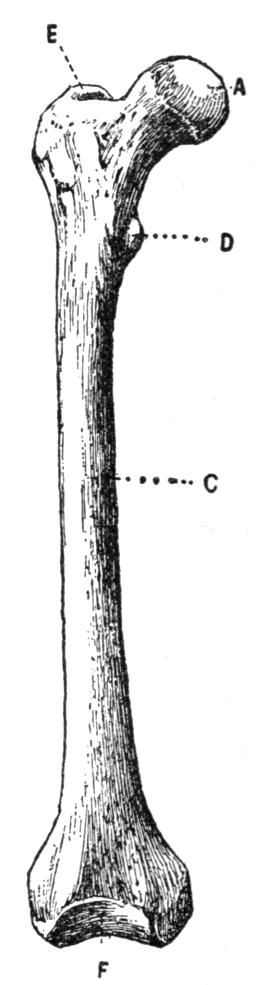

| III. | The Skeleton | H 28 |